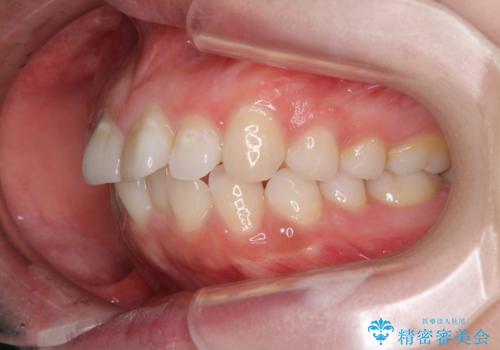

- 前歯のデコボコを気にして来院された患者様です。

当初は口元の突出感はあまり気にされていない様子だったので、インビザラインによる非抜歯矯正をお勧めしたが、ふっくらとした口元を改善したいとのことで、積極的に口元の突出感を改善することとしました。

上下左右第一小臼歯4本の抜歯を行い、ワイヤー装置による矯正治療を行うこととしました。